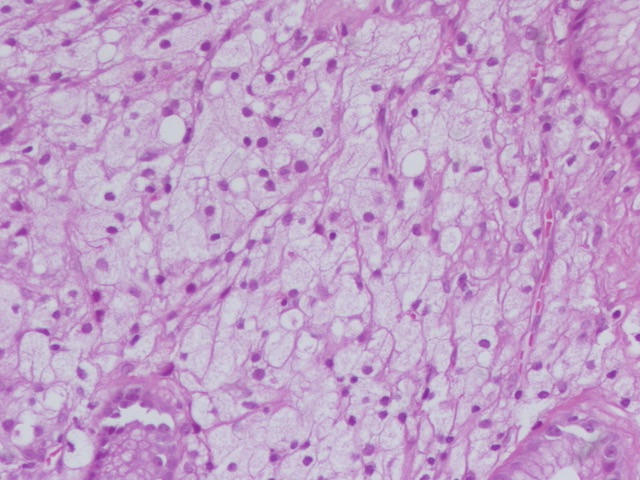

@GladellPaner

Uniquely intricate morphological pattern in #renal tumor! Catchy for #OnePicDx! 🔍 What is your diagnosis on this #nephrectomy #GUPath tweeps? Answer in comment👇👇👇